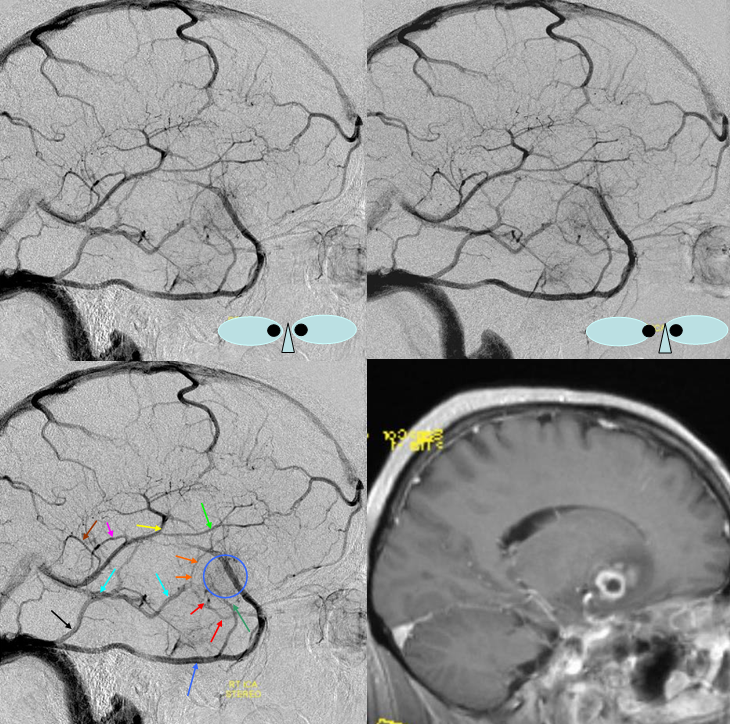

In this patient the inferior sagittal sinus did not develop. Corpus callosum and adjacent territory which may be expected to drain into the inferior sagittal sinus is instead collected by secondarily prominent caudate veins emptying into the thalamostriate and internal cerebral veins. Notice also a well-developed superior petrosal sinus receiving the superficial sylvian system.

Blue Circle=tumor blush. The superficial Sylvian vein is prominent within the circle and extends over the temporal lobe towards the superior petrosal sinus (dark blue arrow). Labbe=black. No Trolard is seen, various superior cortical veins drain into the SSS. Basal vein=light blue, dominant posterior drainage. Very nice demonstration of the deep venous system tributaries. Anterior Septal vein=bright green, capturing territory of hypoplastic anterior cerebral vein. The inferior sagittal sinus is absent. Thalamostriate vein with large longitudinal caudate vein=yellow. Direct lateral vein=pink. Posterior caudate/splenial veins=brown. A prominent Pericallosal Vein empties into a large inferior sagittal sinus. Also note hypoplasia of the superior sagittal sinus proximal to a large superior frontal convexity tributary.